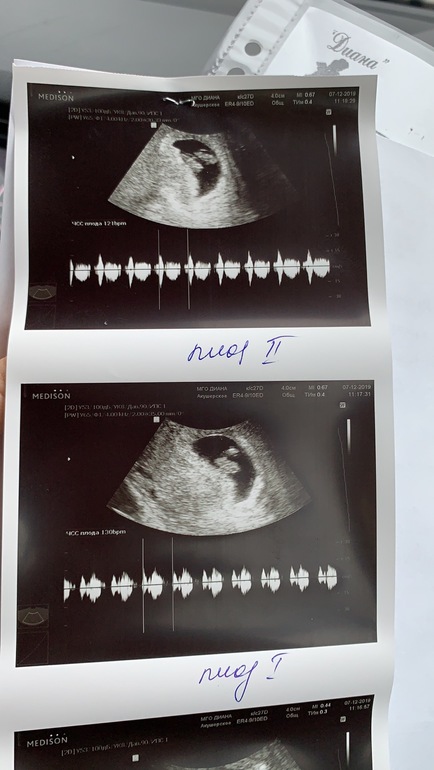

Далее на узи узнаём, что гематома вышла-я уж думала выкидыш. Оказалось, было 2, стал один

Теперь на узи сегодня мы узнали, что у нас... тададаааааам

ДВОЙНЯ!